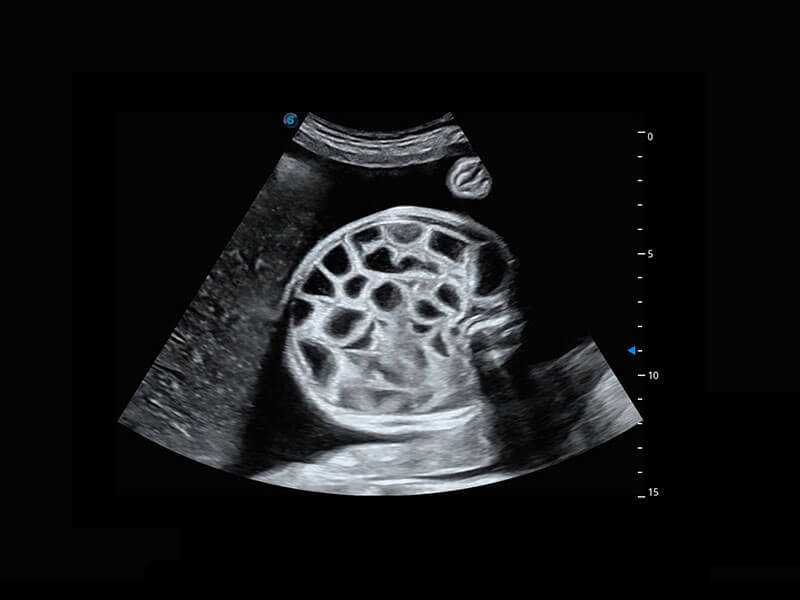

• 右室双出口

• 胎心容积成像